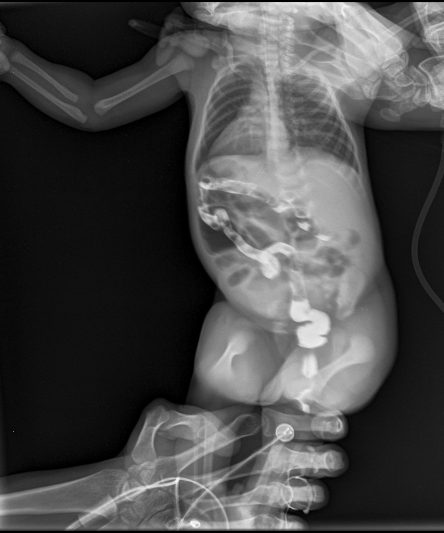

Microskan with Ultra high frequency can take the Lateral Lumbar Spine image of a 90 kg Patient with the correct image receptor